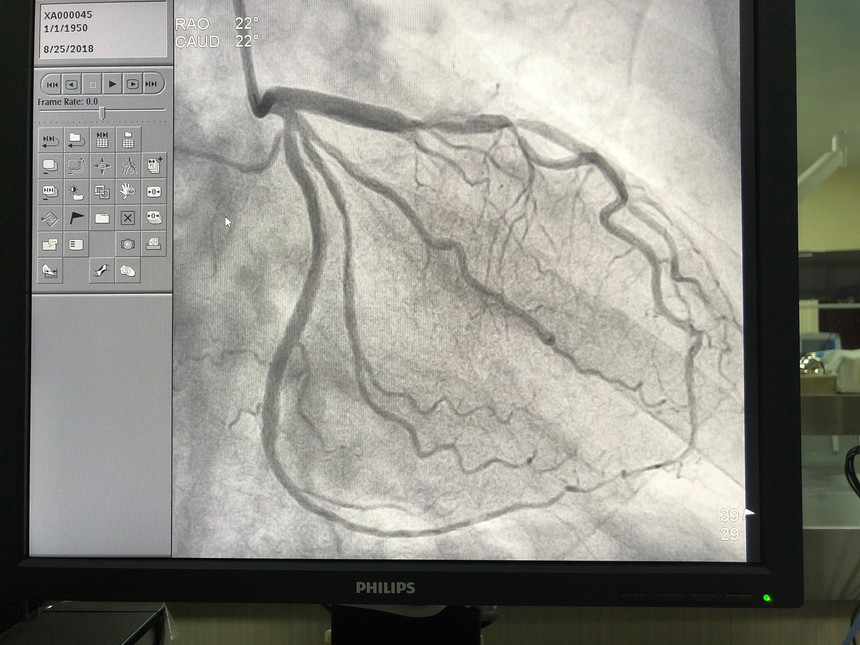

心血管介入中心(DSA)我院心血管介入中心(DSA)于2018年5月創(chuàng)建。在浙大二院長駐和短期10余名幫扶專家的指導(dǎo)下,冠脈造影技術(shù)已成為我院常規(guī)檢查手段,檢查治療病人已超100例,急救了4例急性心肌梗死病人,均未出現(xiàn)如同造影劑過敏、心律失常、動靜脈瘺、冠脈穿孔及心包填塞等嚴重并發(fā)癥。 數(shù)字減影血管造影(DSA)的基本原理是將注入造影劑前后拍攝的兩幀X線圖像經(jīng)數(shù)字化輸入圖像計算機,通過減影、增強和再成像過程來獲得清晰的純血管影像,同時實時地顯現(xiàn)血管影。DSA具有對比度分辨率高、檢查時間短、造影劑用量少,濃度低、患者X線吸收量明顯降低以及節(jié)省膠片等優(yōu)點,在血管疾患的臨床診斷中,具有十分重要的意義。目前臺江縣人民醫(yī)院心臟介入中心配置一臺飛利浦數(shù)字減影血管造影機,有浙大二院心內(nèi)科專家長期幫扶和支持,能開展經(jīng)皮冠狀動脈造影術(shù)、經(jīng)皮冠狀動脈血管成型術(shù)及經(jīng)皮冠狀動脈支架置入術(shù)。

經(jīng)皮冠狀動脈手術(shù)

術(shù)后 |